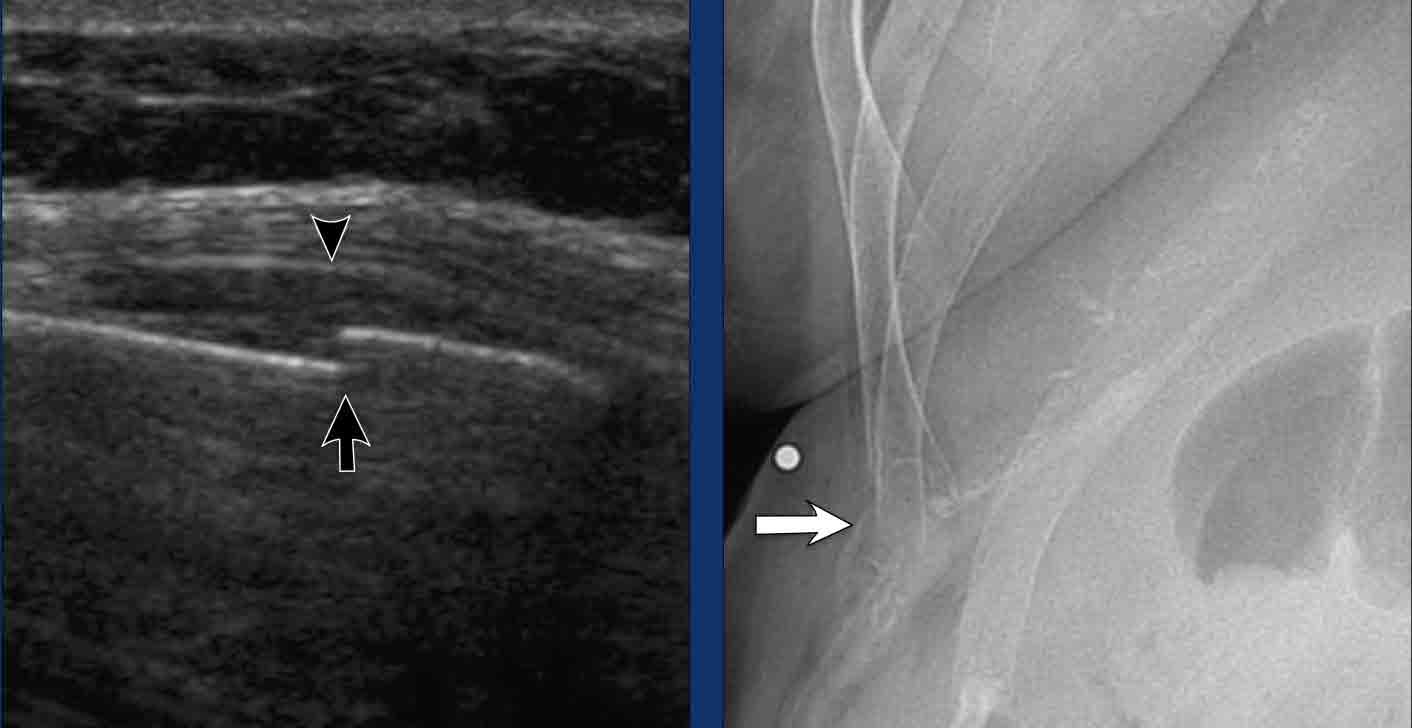

Gãy Xương Sườn

Biểu hiện lâm sàng của gãy xương sườn thường khá điển hình, đặc trưng bởi đau khu trú và đau ngực kiểu đâm chói sau chấn thương ngực trực tiếp hoặc té ngã.

Tuy nhiên, chúng tôi đã gặp một số bệnh nhân gãy xương sườn thấp không được nghi ngờ trước, nhập viện vì đau bụng cấp tính mà không có triệu chứng lồng ngực kèm theo.

Phần lớn các bệnh nhân này không có tiền sử chấn thương, gợi ý rằng các gãy xương sườn này là gãy xương do suy yếu (insufficiency fractures), thường xảy ra thứ phát sau ho mạnh kéo dài. Ở bệnh nhân ung thư, các gãy xương như vậy có thể mang bản chất bệnh lý.

Siêu âm đã được chứng minh là rất hiệu quả trong việc phát hiện gãy xương sườn, với độ nhạy vượt trội hơn so với X-quang thường quy.

Bằng cách quét vùng đau với đầu dò đặt song song với trục dài của xương sườn, gãy xương có thể được xác định qua hình ảnh gián đoạn của vỏ xương phía trước tăng âm, thường kèm theo tụ máu.

Mặc dù siêu âm là công cụ chẩn đoán có giá trị, CT vẫn cho độ chính xác cao nhất trong phát hiện gãy xương sườn, đặc biệt khi quan sát bằng cửa sổ xương phù hợp.

Trường hợp lâm sàng

Bệnh nhân nữ 84 tuổi, gãy xương sườn, nhập viện vì đau cấp tính vùng bụng trên bên phải. Bệnh nhân phủ nhận tiền sử chấn thương.

Hình ảnh học

- Siêu âm cắt ngang đúng tại vị trí đau nhiều nhất cho thấy hình ảnh gãy xương sườn di lệch vừa (mũi tên) kèm theo tụ máu nhỏ (đầu mũi tên). Không phát hiện bất thường nào khác.

- X-quang xác nhận gãy xương cấp tính đầu xa xương sườn 11 phía trước (mũi tên)